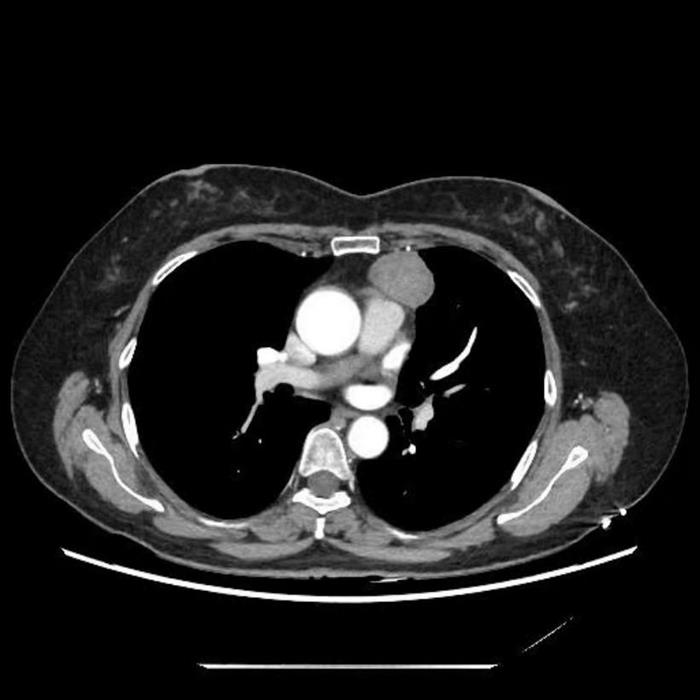

近日,遂宁市中心医院胸外科周海宁团队与麻醉科紧密协作,成功开展一例“非气管插管麻醉(Tubeless)下经皮天平拉钩辅助胸腔镜经剑突下前纵隔肿物切除术”。该技术的成功实施,标志着医院在纵隔疾病微创治疗领域取得新突破,为患者提供了更加安全、高效和舒适的手术选择。

患者为一名43岁女性教师,因体检发现纵隔肿物5个月入院。出于对术后可能影响发声、耽误教学工作的顾虑,患者一度不愿接受手术。传统胸腔镜手术虽属微创,但仍存在器械干扰、视野局限等操作难点。本次采用的“Tubeless麻醉+经皮天平拉钩”技术体系,有效解决了上述问题,实现了更优的手术显露与更小的生理干扰。

该项创新技术通过特殊设计的“天平拉钩”装置均匀分散牵拉力,稳定抬升胸骨,为术区提供清晰、开阔的手术视野,从而精准完整切除病变组织,并且还避免了传统牵拉方式对胸骨的损伤。结合Tubeless麻醉技术,术中不再需要气管插管,减轻了术后咽喉不适和呼吸道并发症风险。手术仅通过剑突下约3–4厘米小切口完成,无需留置胸腔引流管及导尿管,显著减轻了术后疼痛,加速患者康复。整台手术历时约1小时,出血量少,患者术后疼痛轻微,可早期下床活动,并于术后48小时顺利出院。